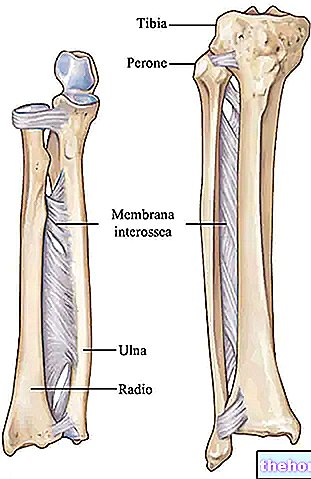

Анатомия фибулы: Подробные фотографии и схемы